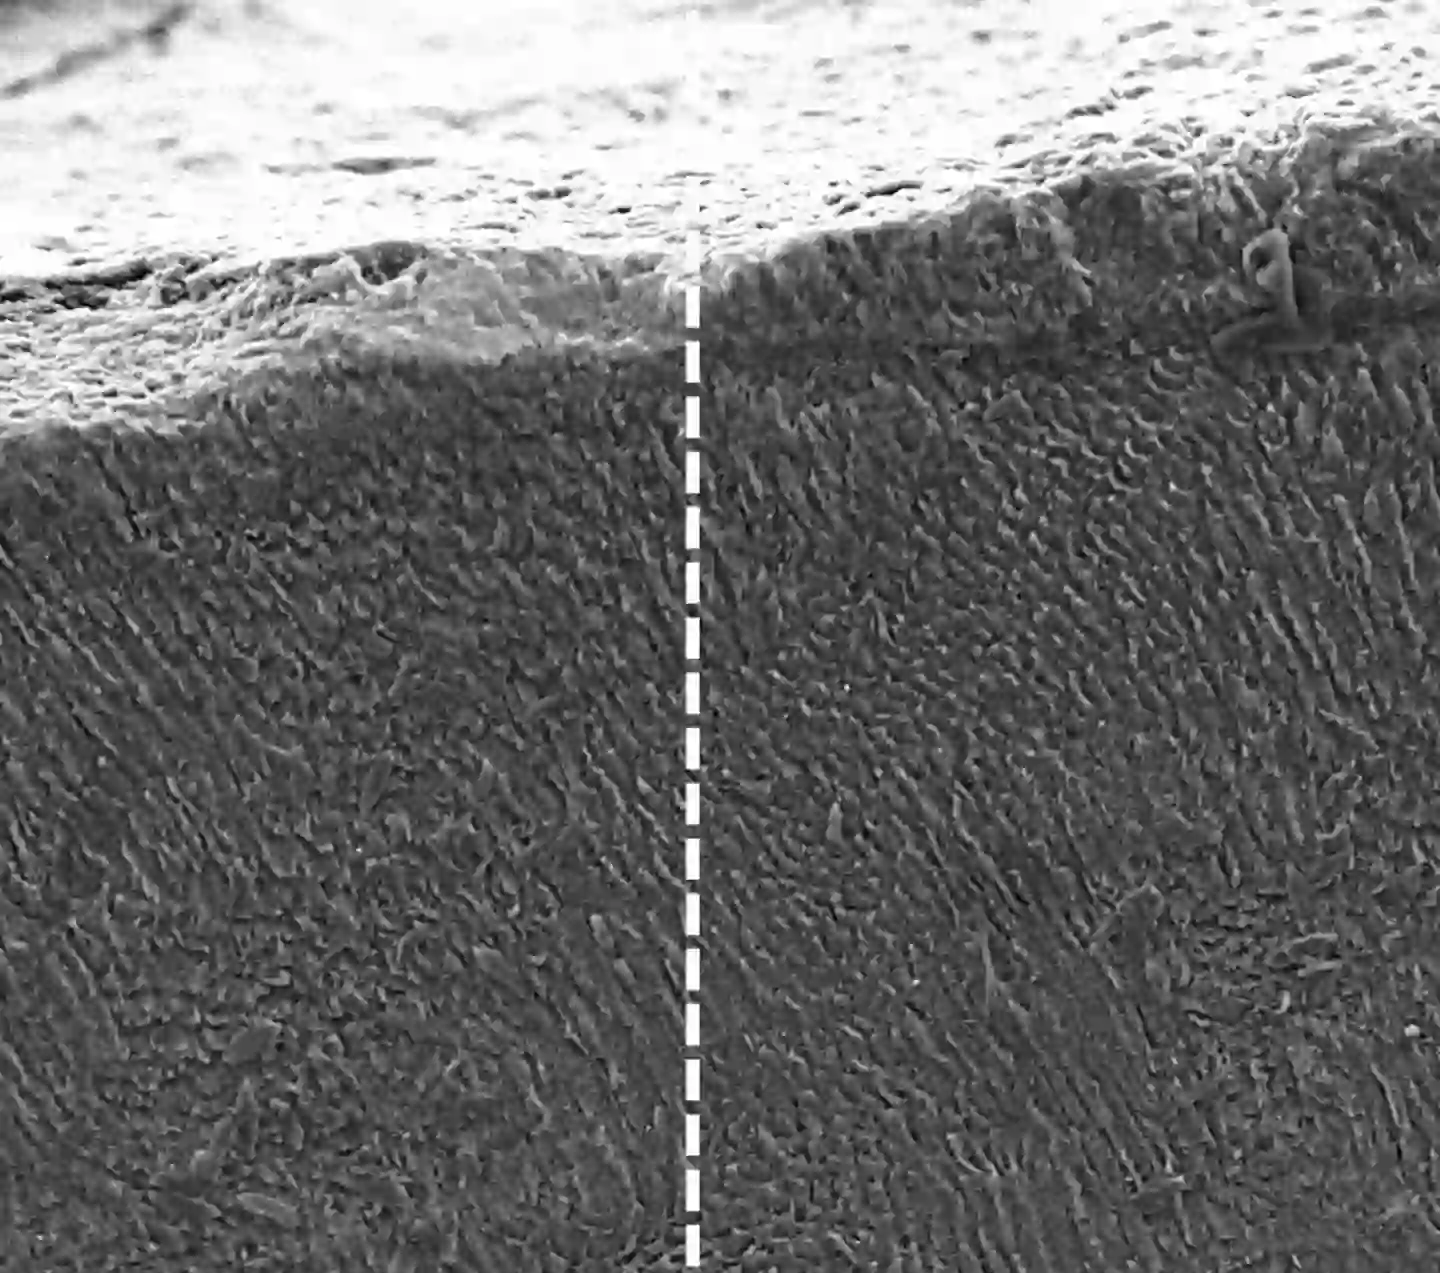

The left side shows the surface of a tooth before the keratin treatment, while the right shows after (King’s College London)

When it comes into contact with the minerals which are naturally present in our saliva, it forms a dense mineral layer which ‘mimics the structure and function of natural enamel’.

In their findings, which were published in Advanced Healthcare Materials, the team explained: “While fluoride toothpastes are currently used to slow this process, keratin-based treatments were found to stop it completely.

“Keratin forms a dense mineral layer that protects the tooth and seals off exposed nerve channels that cause sensitivity, offering both structural and symptomatic relief.”